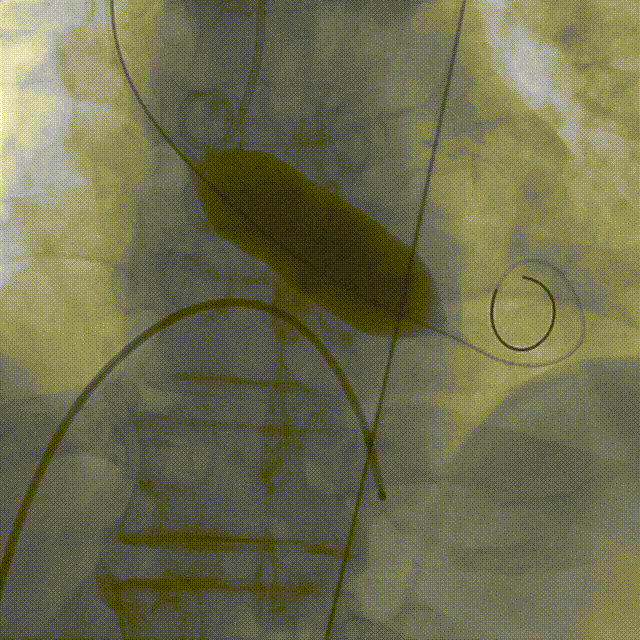

TaurusNXT植入过程

术中影像

瓣膜释放至工作位造影